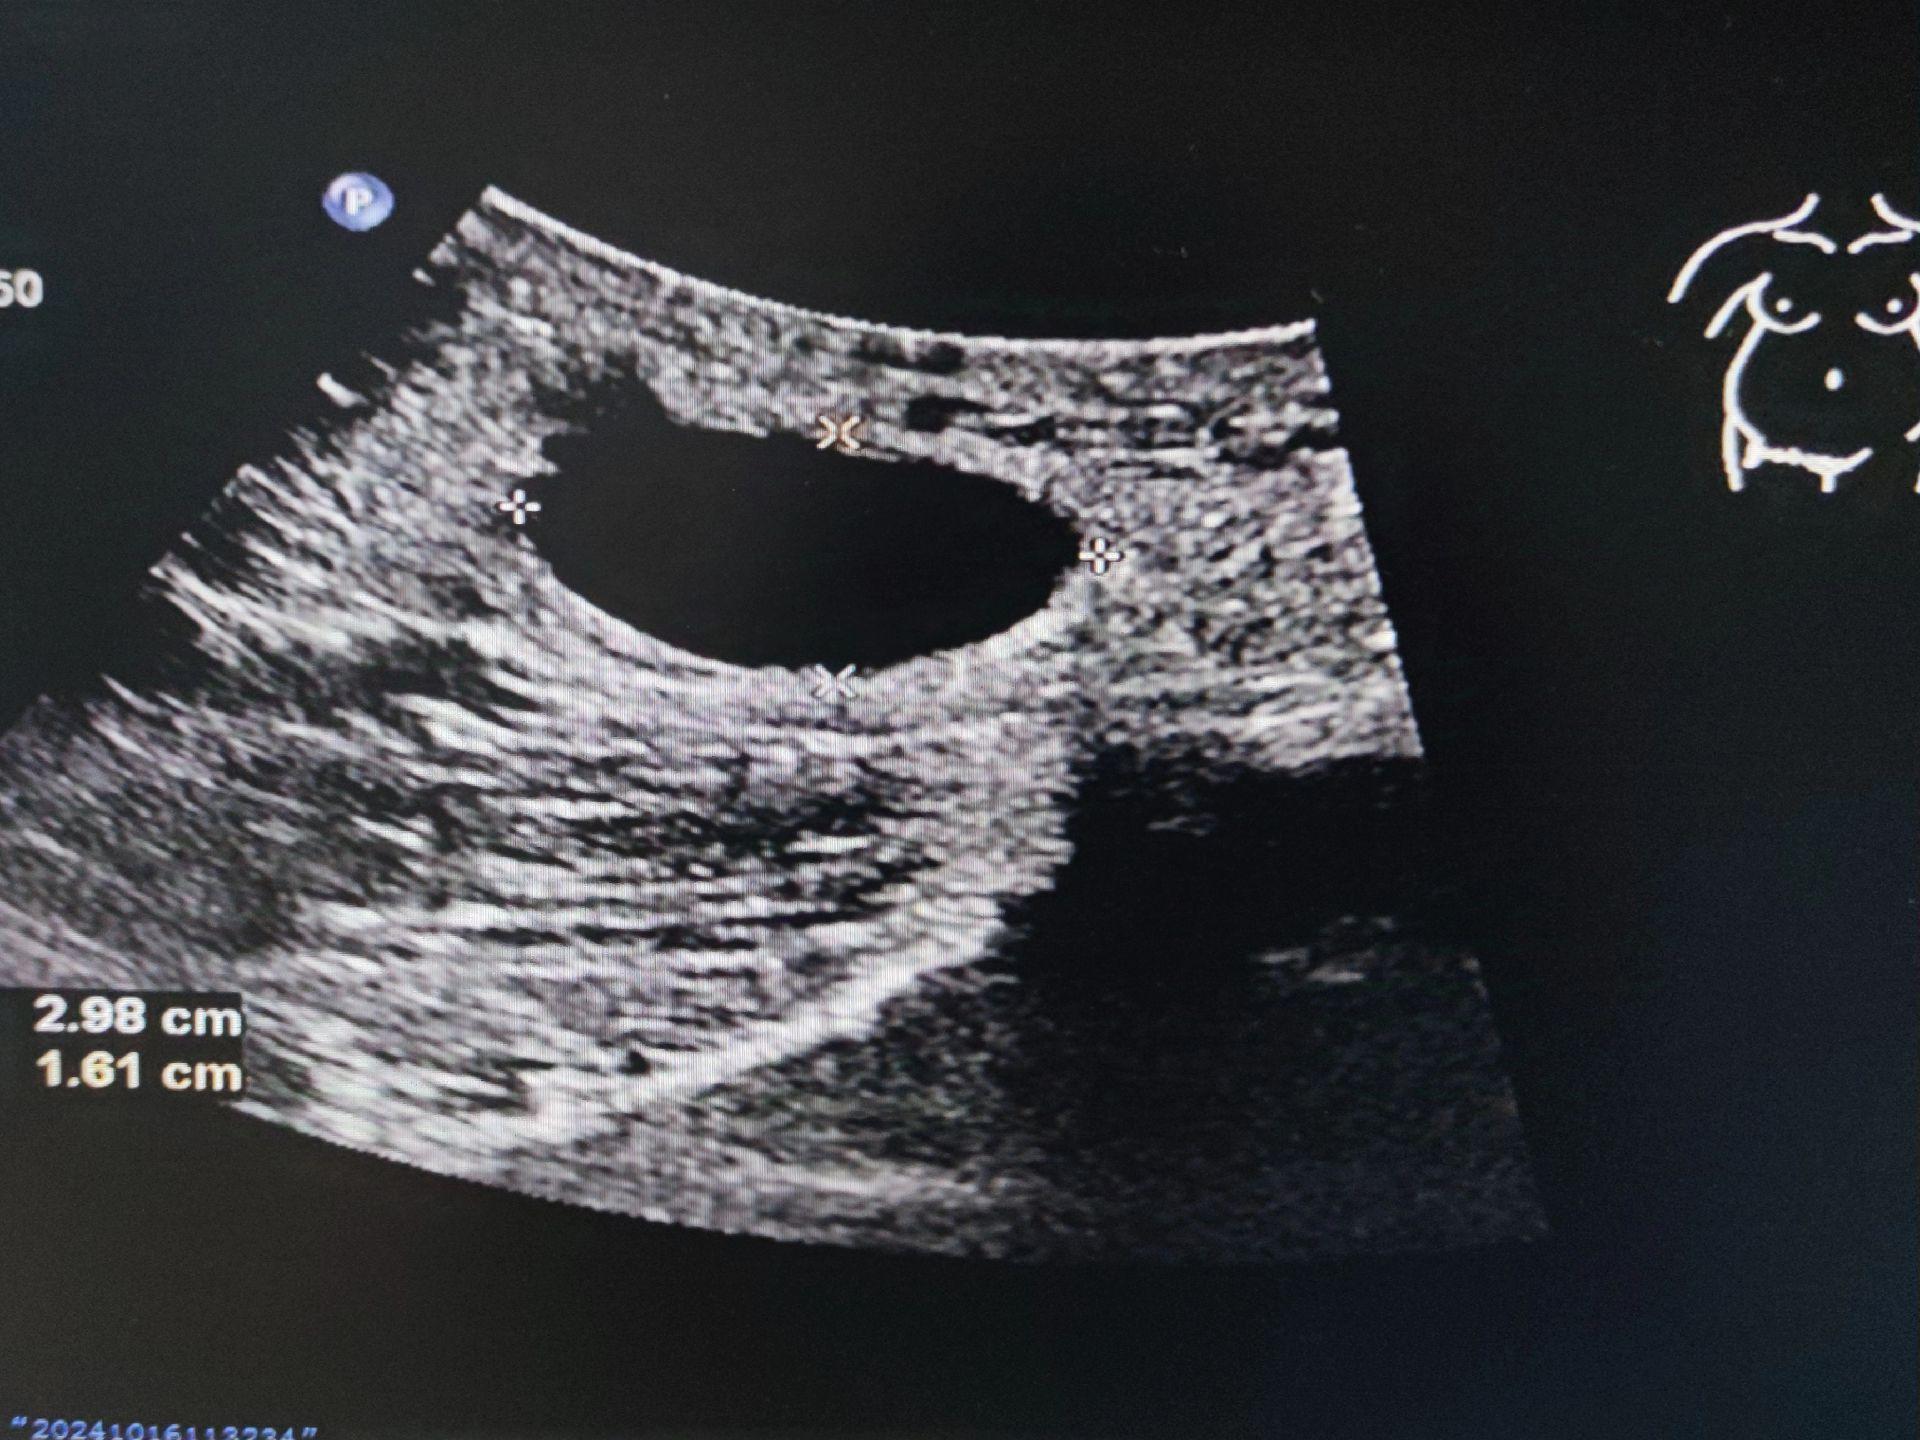

子宫圆韧带囊肿。女,41岁,腹股沟去包块来检查 子宫圆韧带囊肿又叫Nuck囊肿,少见。囊肿大小及形态不随体位改变而变化,有别于腹股沟斜疝